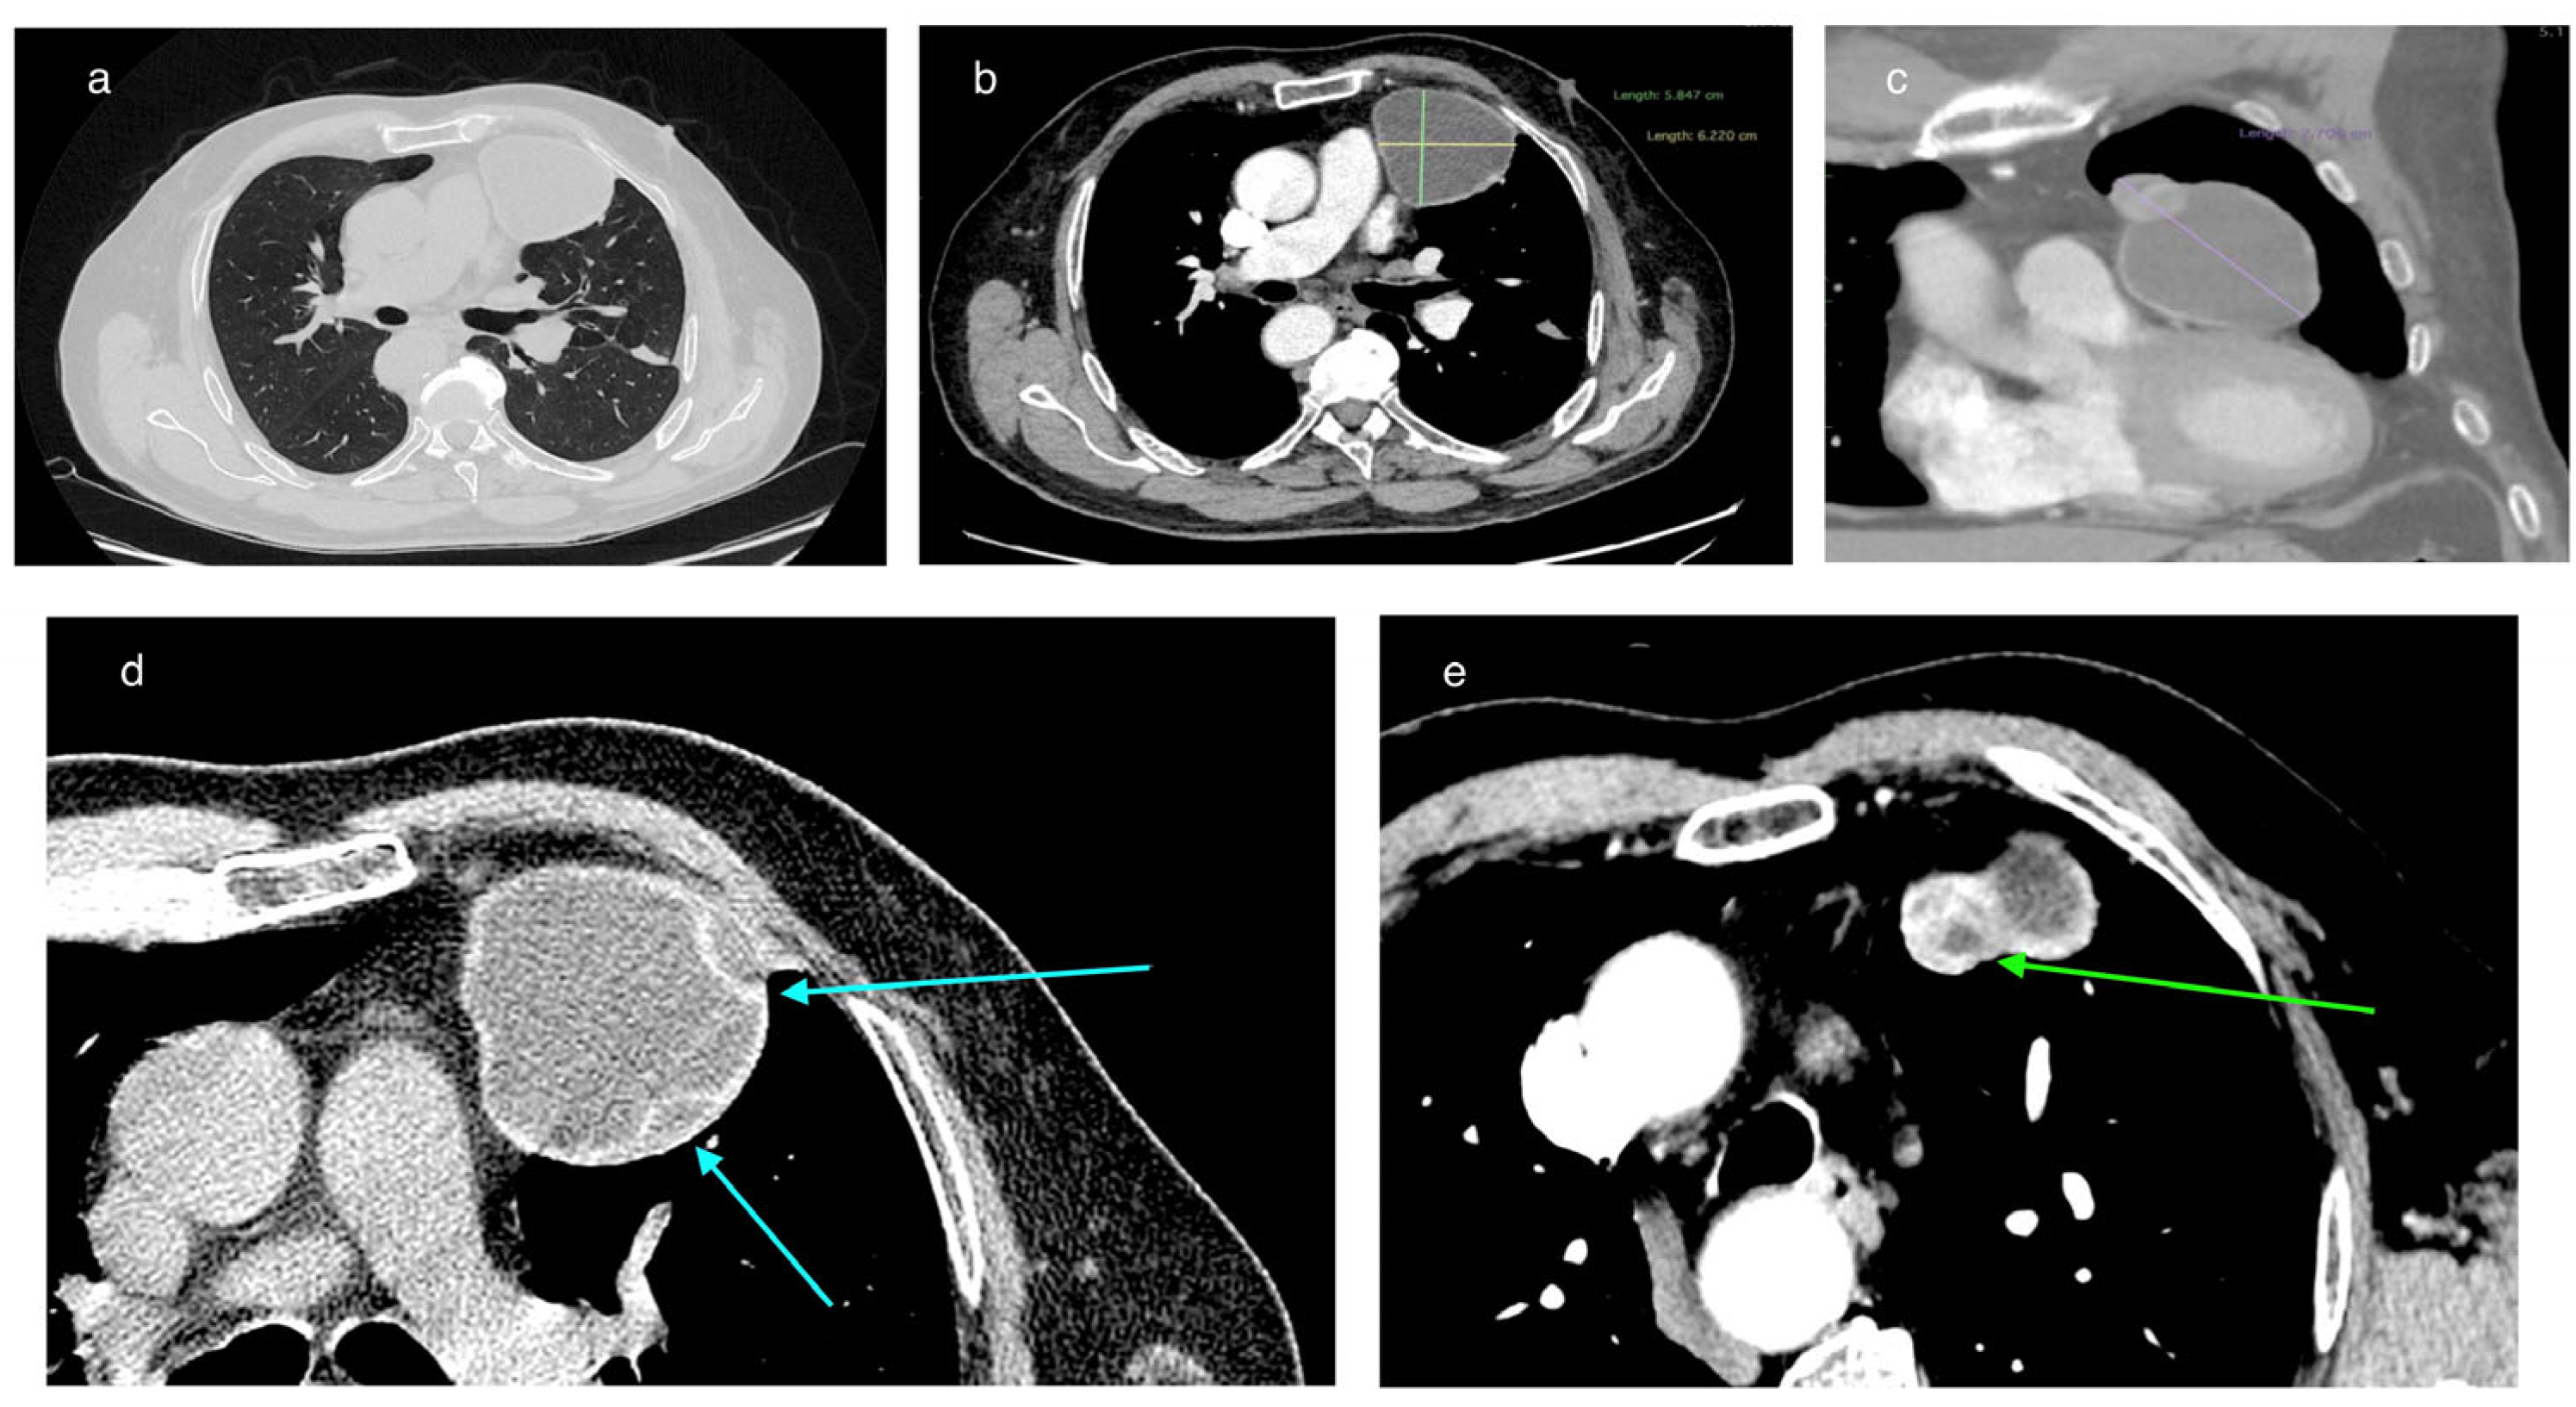

In February 2025, a 69-year-old patient was admitted to the Department of Thoracic Surgery and Transplantology at Pomeranian Medical University in Szczecin for surgical treatment of a mediastinal lesion. Upon admission, the patient reported intermittent chest pain. Chest computed tomography (CT) performed 25 November 2024 had revealed a well-defined, cystic, hypodense lesion in the left anterior mediastinum with an attenuation of 3–7 Hounsfield Units (HU) and measuring (in vivo) approximately 58 mm × 62 mm (axial plane) × 77 mm (long axis) (Figure 1). The cyst walls measured up to 4 mm and had a segmental detached membrane forming thin, flattened pseudo-vesicles (Figure 1). At the upper pole of the cyst, a heterogeneous dense (50 HU) nodular mass exhibited mild contrast enhancement and measured approximately 25 mm in diameter (Figure 1). These findings were equivocal and lacked distinctive features to establish the diagnosis of a pericardial cyst, thymic cyst, hamartoma, or cystic proliferation (lymphoma/meta) of the pericardium or lung. Based on the patient’s history of previous left-sided chest CE and left posterolateral thoracotomy, the differential diagnosis of the mediastinal lesion detected >50 years later should include hydatid cyst.

On chest CT, the cyst in the anterior mediastinum of our patient demonstrated features compatible with transitional stages of the WHO-IWGE classification. In this classification, the cyst morphology is visualized using imaging techniques. The detached internal membrane forming flattened pseudo-vesicles corresponds to CE3a (‘water-lily sign’), while the enhancing nodular mass adjacent to the cyst wall suggests a CE3b lesion (Figure 1). According to WHO-IWGE, CE3a and CE3b are transitional stages, distinct from CE1–CE2 (active unilocular or multivesicular cysts) and CE4–CE5 (inactive, degenerative, or calcified cysts). We emphasize that these assignments were derived solely from imaging evidence. Histopathology confirmed echinococcal infection but does not provide staging information.

Figure 1. CT imaging of a cyst in the left anterior mediastinum. (a) Axial chest CT images in the lung window without contrast enhancement. (b) Contrast-enhanced axial chest CT images with the long axis measurement. (c) Contrast-enhanced coronal chest CT images with delineation of its long axis measurement. (d) Focal detachment of the cyst’s internal wall – indicated by the arrow. (e) Contrast-enhanced nodular mass adjacent to the fluid-filled cyst – indicated by the arrow.